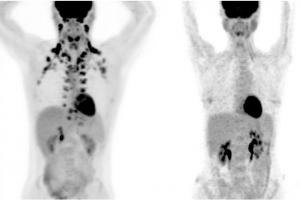

MALADIE CORONARIENNE : La tomodensitométrie, une alternative viable au cathétérisme

MALADIE CORONARIENNE : Précoce, elle prépare le lit de la démence

Actualité publiée le 13/02/2024MALADIE CORONARIENNE : Découverte de nouvelles cibles de prévention primaire